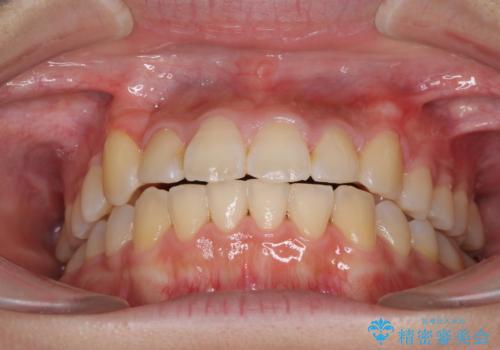

- 2年10ヶ月

治療の度に歯列が改善していったため、長期間の治療も楽しく過ごしていいただき、満足のいく仕上がりとなりました。